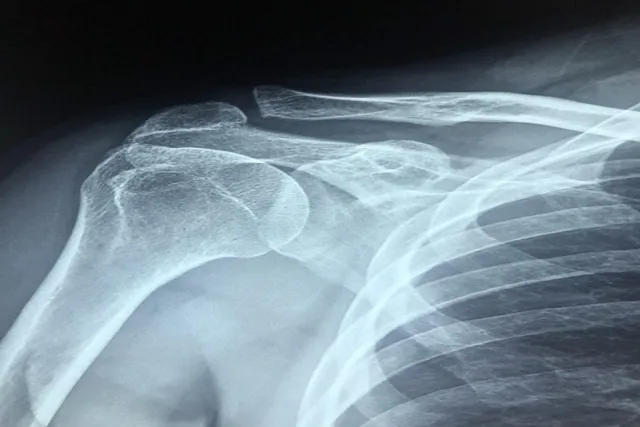

어깨 석회질을 정확히 진단하기 위해서는 몇 가지 방법이 필요합니다. 일반적으로 의사는 다음과 같은 방법을 사용합니다. 첫째, 증상에 대한 상세한 물음과 신체 검사가 이루어집니다. 둘째, X-ray 촬영을 통해 석회석의 유무를 확인합니다. 마지막으로, MRI 촬영을 통해 부상 정도를 평가하기도 합니다.

어깨 석회질, 혹은 석회질성 건염은 어깨의 힘줄에 칼슘이 쌓이면서 발생하는 질환입니다. 이는 주로 어깨의 회전근개에 영향을 미치며, 통증을 동반합니다. 원인은 여러 가지가 있지만, 주로 반복적인 적응과 노화에서 기인합니다. 이로 인해 어깨 통증 완화를 위해 적절한 치료가 필요합니다.